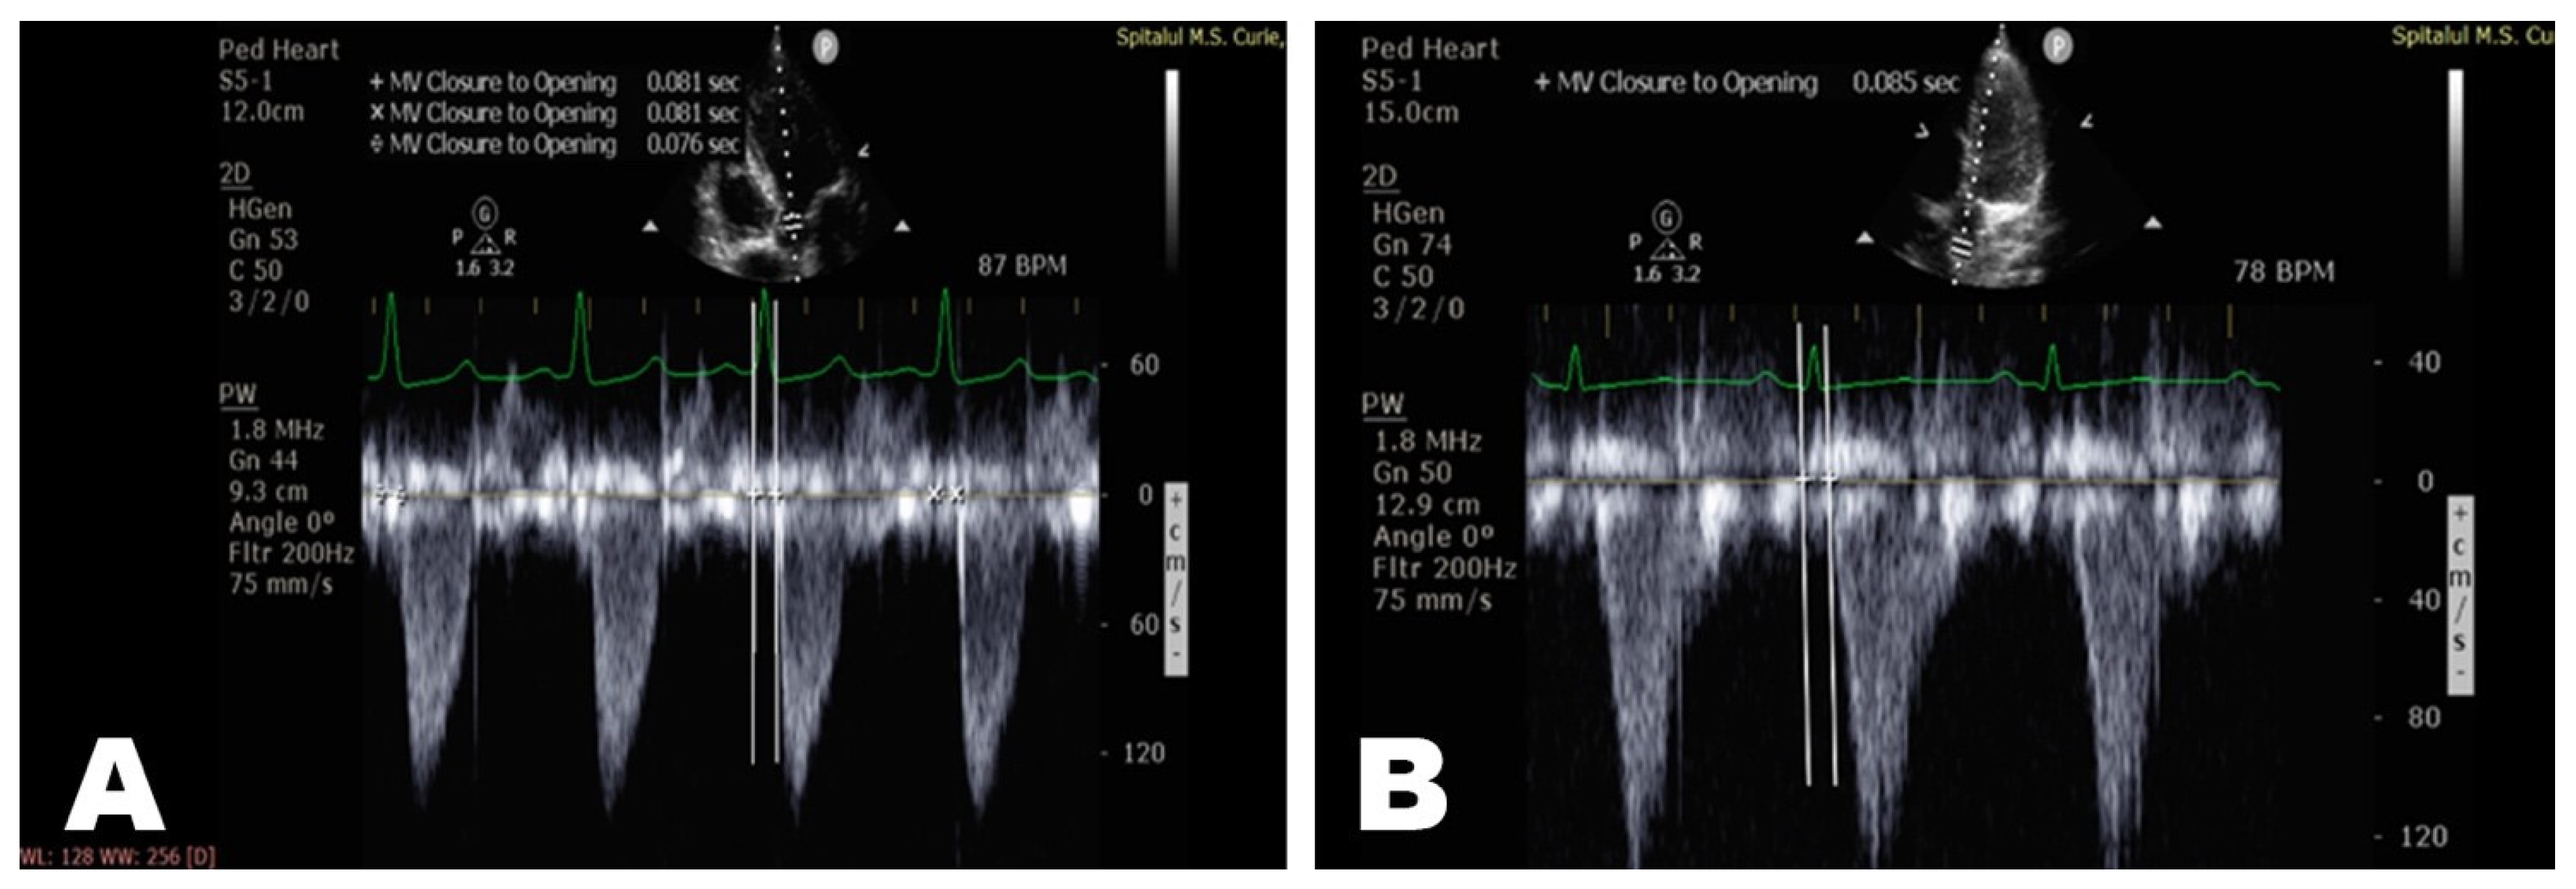

| T0(QRS—AoV) (msec) | 70 [63.9;80.1] | 65.7 [63.75;72] | 74.47 [60;92] | 72 [64;80] |

| T1(QRS—AscAo) (msec) | 75 [67;84] | 70.8 [69.75;75.25] | 80.18 [66;97.5] | 76.6 [67;84] |

| T2(QRS –DescAo) (msec) | 109 [98.9;117.1] | 107.3 [104.3;115] | 118.8 [101;136] | 104 [92;113] |

| PWV—AscAo (m/sec) ** | 4 [3.3;4] | 3.65 [3.3;4] | 3.44 [3.3; 4] | 4.53 [4; 6.92] |

| PWV—DescAo (m/sec) *** | 4.05 [3.61;4.75] | 3.795 [3.58;4.39] | 3.73 [3.46;4.015] | 5.279 [4.64;5.83] |